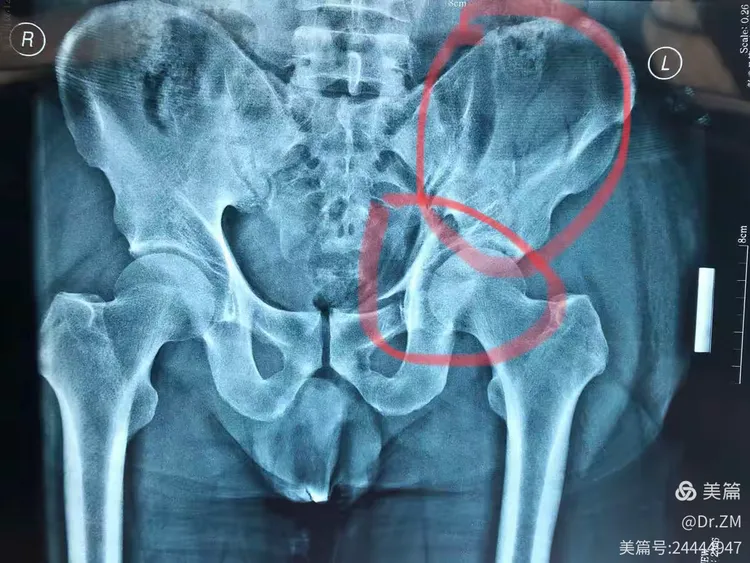

请问右髂骨是哪个部位?右髂骨在哪?[s0]右侧髂骨图[s1]1,右侧髂骨骨折;2.2,左[s2]患者的临床表现及辅助检查结果,诊断为右髂骨骨折,遂将患者收入我科。二、治疗经过入院后,与患者及家属进[s3]1,右侧髂骨骨折;2.2,左[s4]右侧髂骨在哪个位置示意图[s5]右侧髋臼及髂骨病变.[s6][已会诊] 右侧髂骨占位性病变[s7]右侧髂骨 来自网易[s8]右侧髂骨 来自网易[s9]右髂骨骨折术后切口不愈合二个月[s10]镜湖答疑跑步后膝盖疼怎么办运动时候髋关节疼怎么办练普拉提后髂骨疼[s11]右侧髂骨 来自搜狐网[s12]右髂骨翼骨折用手术吗?[s13]骨盆多发骨折:骨盆x线片及骨盆ct平扫可见右侧髂骨、右侧耻骨上下支多发骨质中断[s14]右侧髋臼及髂骨病变[s15]右侧髂骨 来自搜狐网[s16]从片子和触诊上看,她的诊断结果是这样的:右侧髂骨比较严重外旋,左侧[s17]右髂骨在哪腰部以下臀部以上的骨头就是髂骨,所以右髂骨在髂骨右侧。髂[s18]骨二科持续运用新技术普惠广大患者[s19]陈大哥因外伤导致右髂骨骨折,保守治疗效果也很好![s20]右侧髂骨 www.cn-healthcare.com[s21]【典型案例】骨盆、右髂骨、右坐骨骨折[s22]妻子患病髂骨占位——跪求!!大家帮看看长了什么东西[s23]右侧髂骨 个人图书馆[s24]【原创】右髂骨病变,有病理,一周后公布。[s25]。骶骨还有没有骨折?不太明显;左侧髂骨翼也不太像骨折。ct证实一下。[s26]右侧髂骨 搜狐网[s27]患者为高处坠落伤,左侧骨盆髂骨翼及髋臼前后柱粉碎骨折。这类损伤对患者致残率高,又因其解剖结构原因,周[s28]《上海髋撞就诊经历—待术中》4[s29]右侧髂骨慢性骨髓炎[s30]右侧髂骨 来自网易[s31]右侧髂骨 知乎[s32]本人首例 改良stoppa 髂骨窗入路 治疗髋臼骨折[s33]右侧髂骨 www.haodf.com[s34]图片[s35]3D REC (13).jpg[s36]法斗右腿髌骨脱位救救孩子吧[s37]左侧髂骨粉碎性骨折、右侧耻骨上下支骨折[s38]左髂骨粉碎性骨折,骶1,2椎体骨折,左侧耻骨上下支骨折,耻骨联合分离[s39]